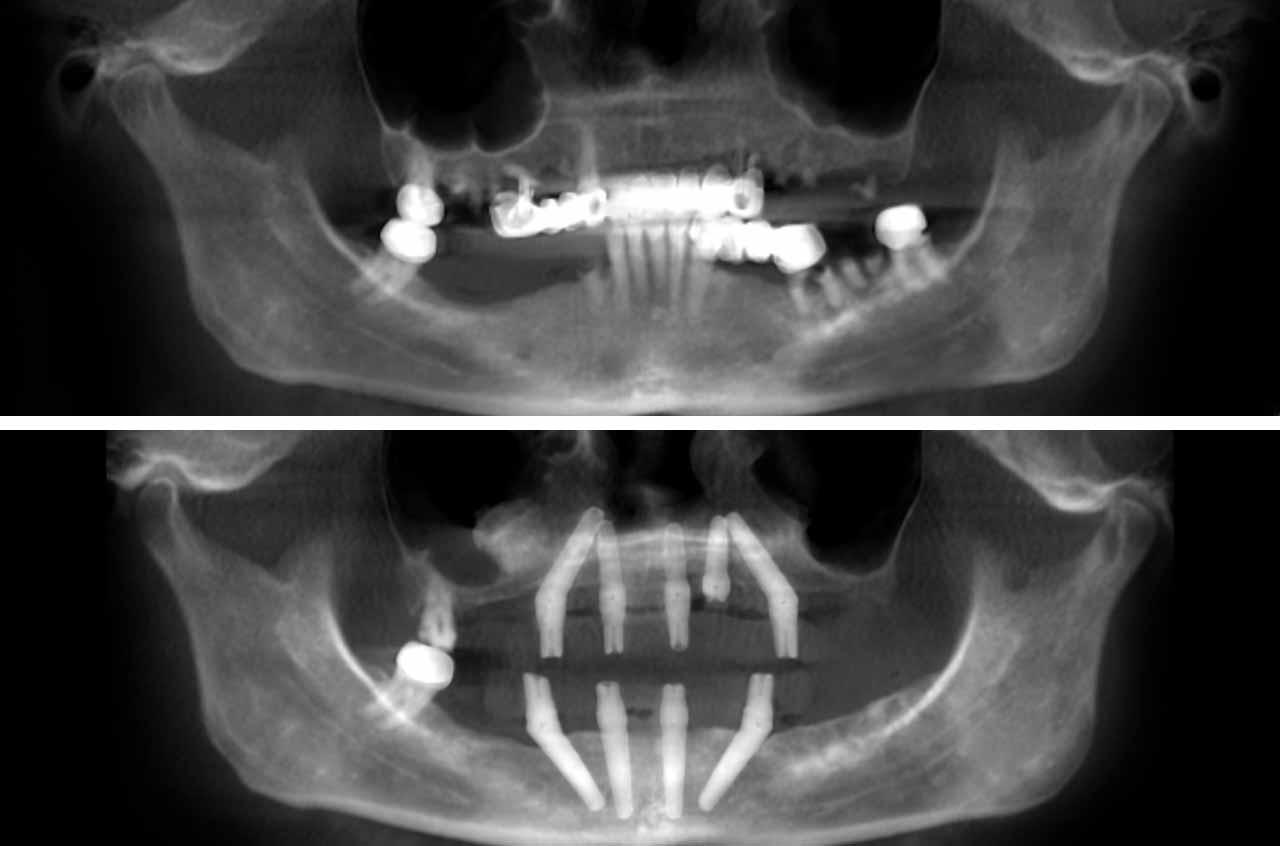

What is the All-on-4 Technique?

All-on-4 is a revolutionary dental implant technique that uses just four strategically placed implants to support a full arch of replacement teeth. The posterior implants are angled at 30-45 degrees to maximize bone contact and avoid anatomical structures like the maxillary sinus or inferior alveolar nerve. This innovative approach allows for immediate loading with a temporary prosthesis, providing same-day teeth and eliminating the need for lengthy healing periods between procedures.